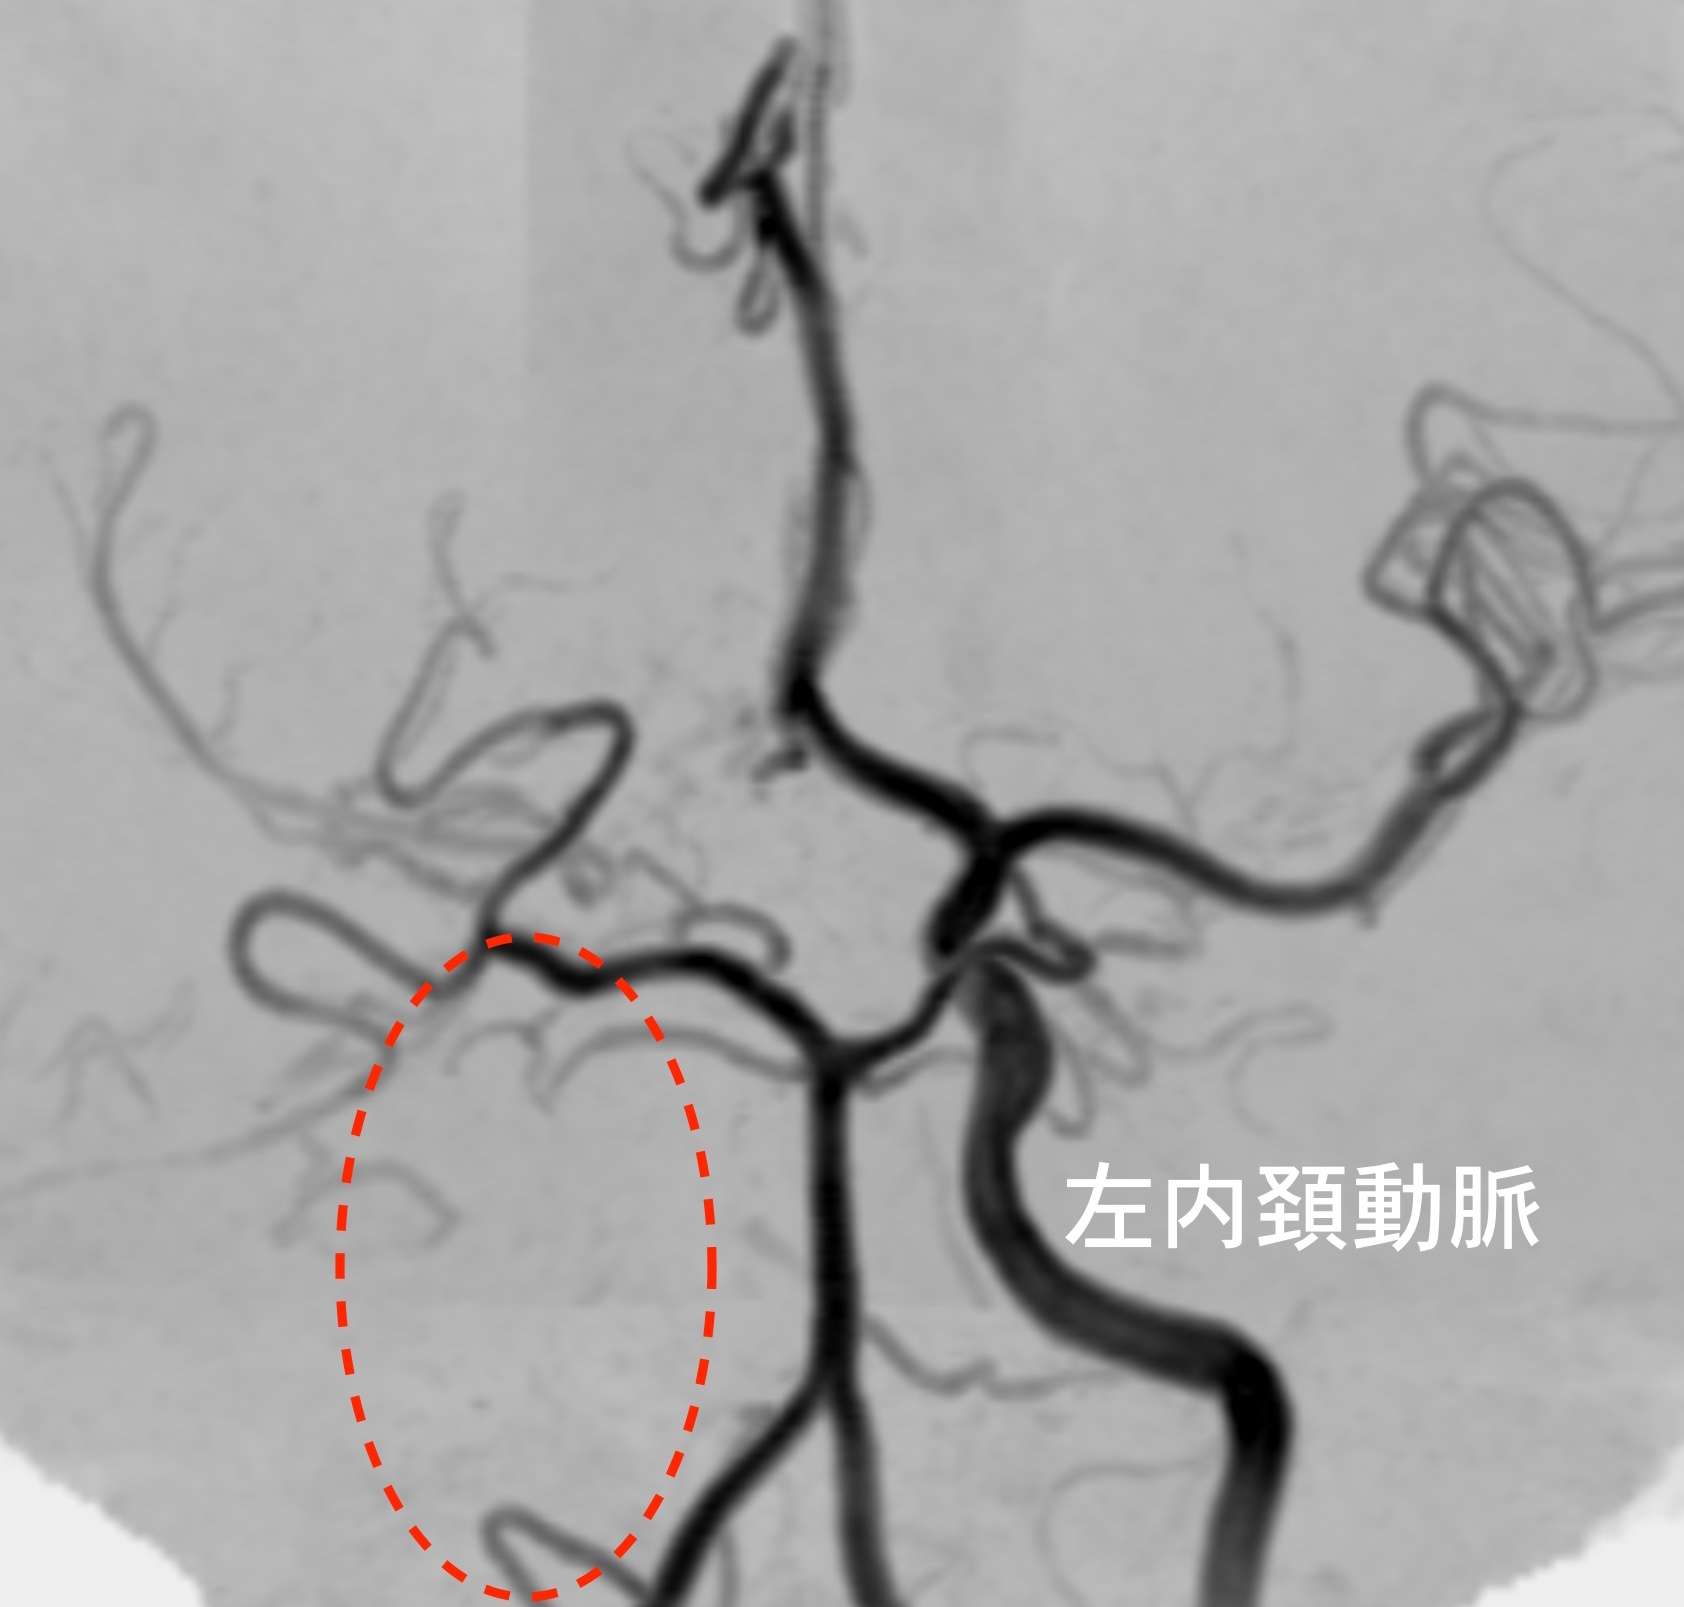

※下は他のもやもや病と片頭痛のある方の画像で、左側の内頚動脈が詰まっています。

血管が詰まり血流が悪くなると、それを補おうとして毛細血管が発達してきます。そして、その状態がもやもやと見えるため、「もやもや病」と名付けられました。若い方の脳梗塞や脳出血の原因となります。遺伝子が特定されていますが、必ずしも全員が発病するわけではありません。